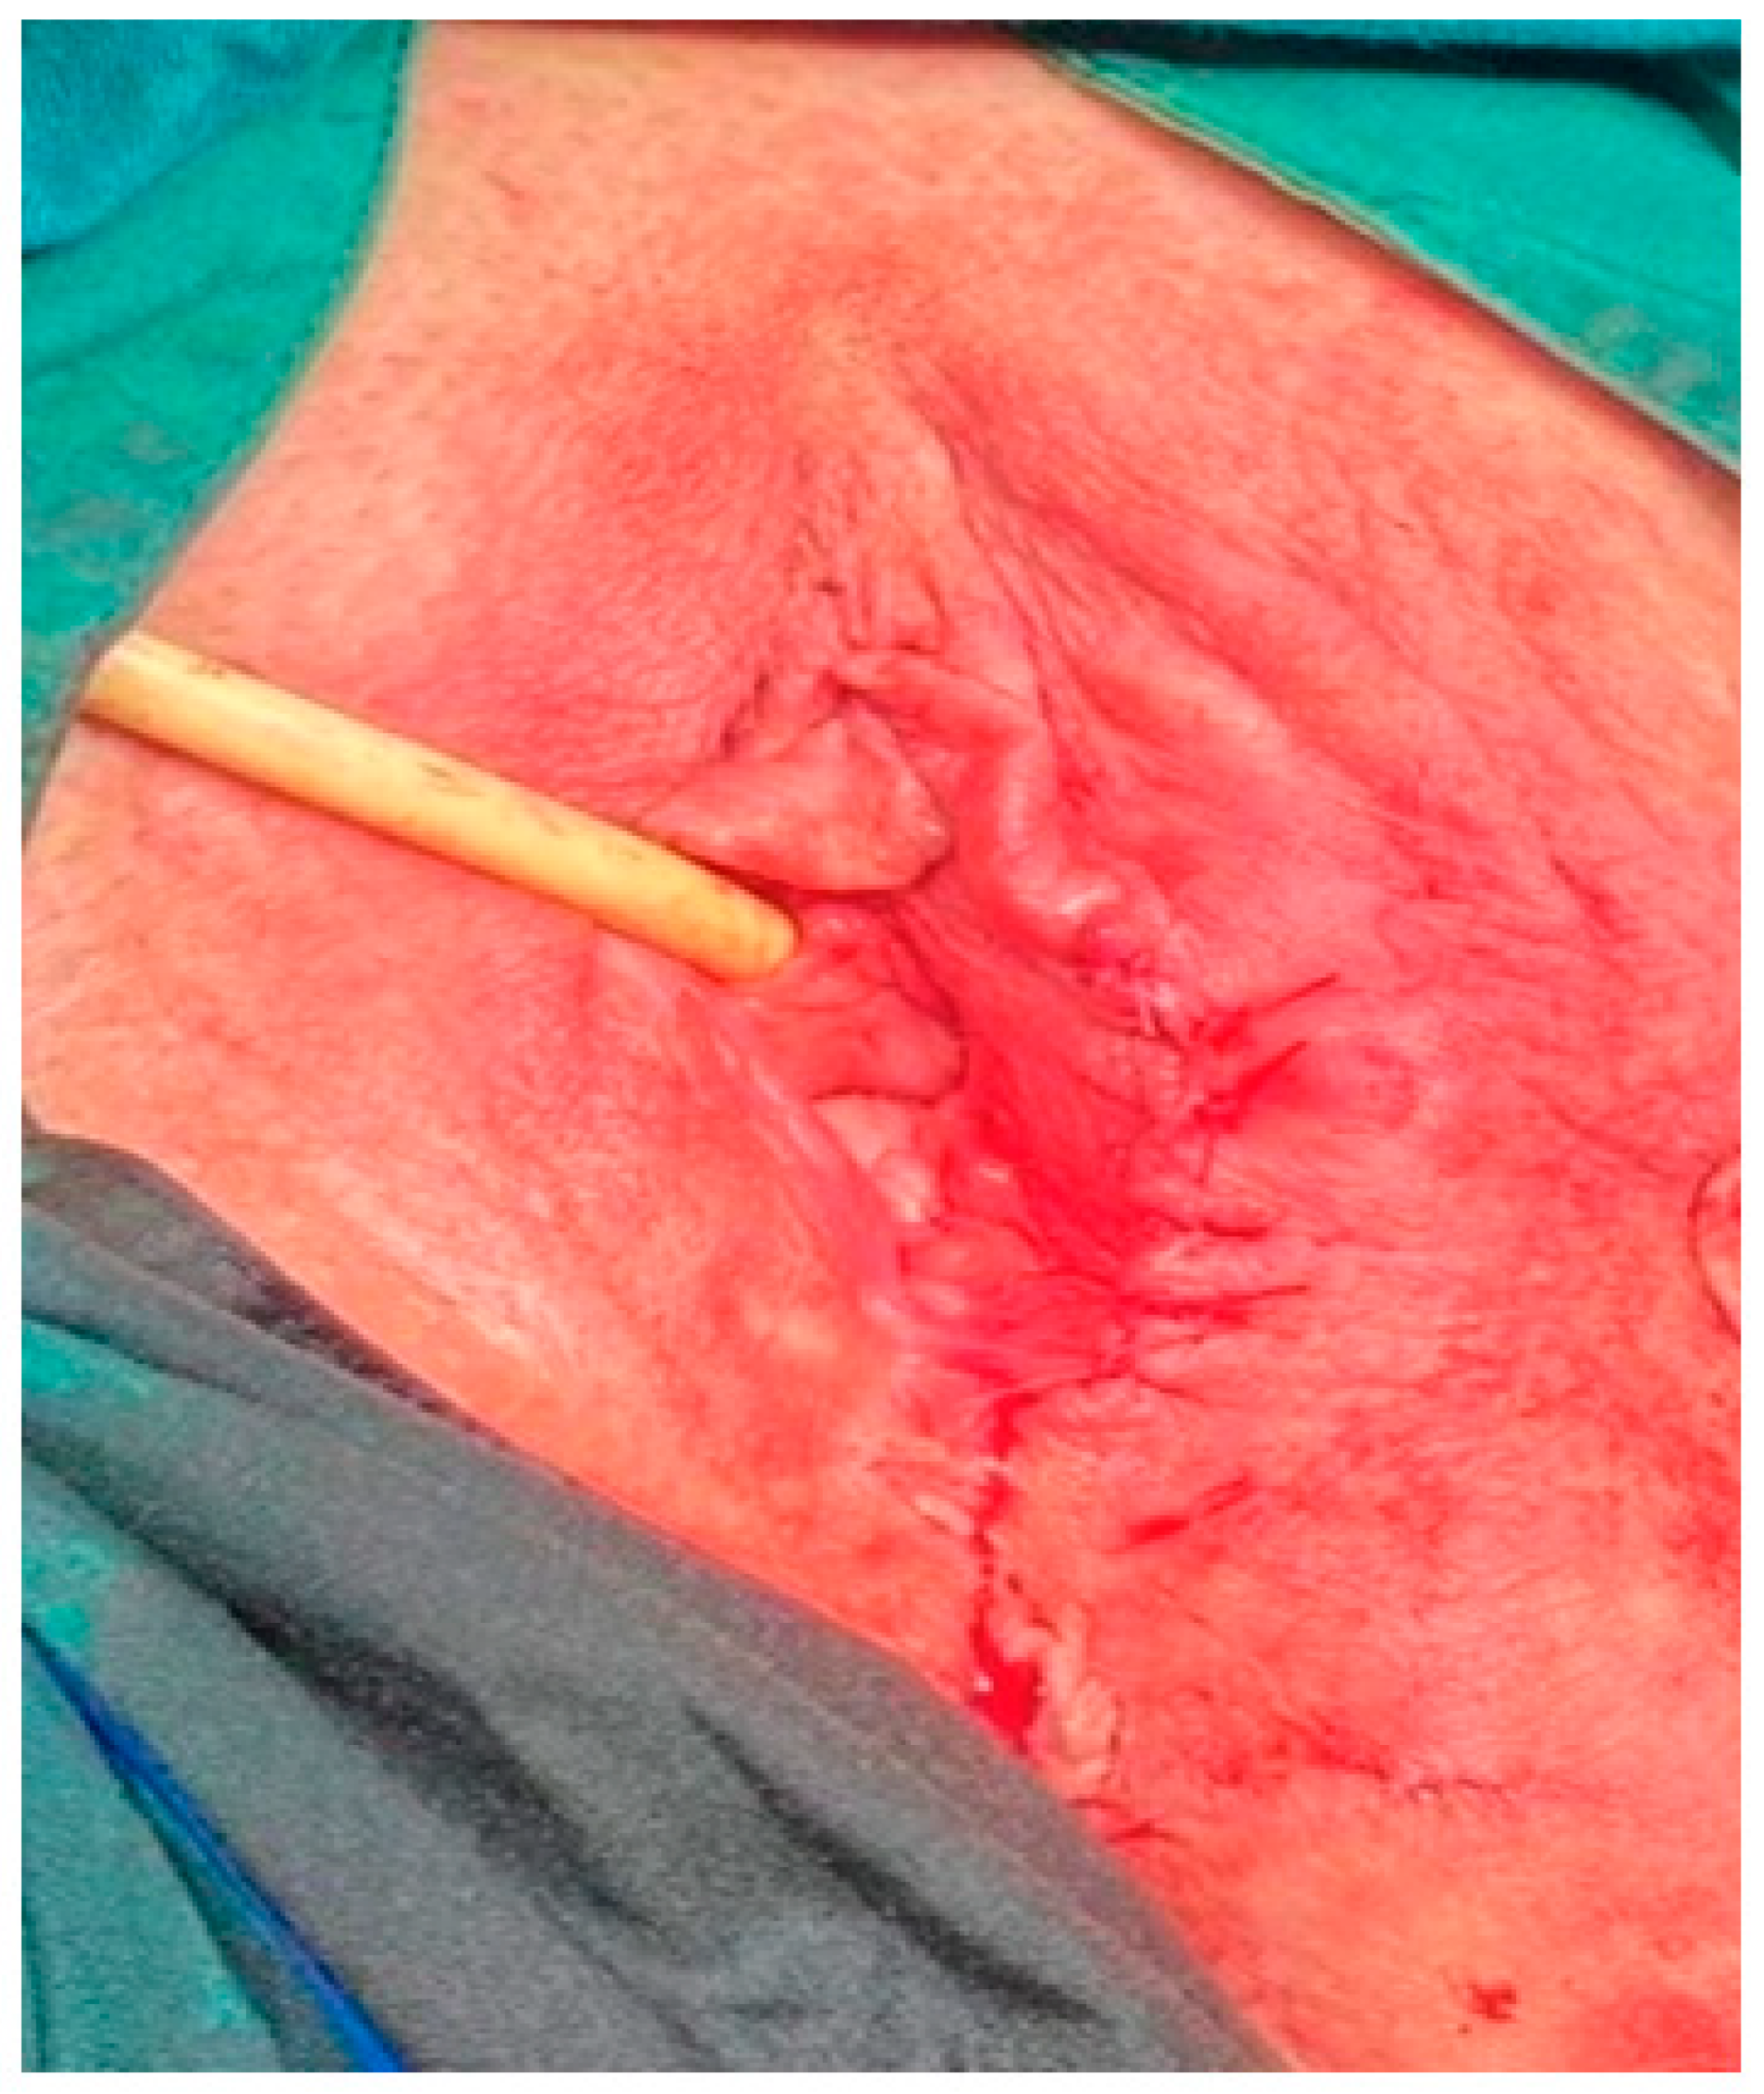

We present a clinical case of an aggressive angiomyxoma located in the left greater labial area in a 50-year-old woman, initially diagnosed as a left inguinal hernia. The patient was referred to a surgeon with a suspected left inguinal hernia. The surgeon rejected the diagnosis and the woman was referred for a consultation with a gynecologist. The history revealed the following information: the patient was 50 years old and had no family history. She reported two children born by caesarean section in 1995 and 2003 and regular menstrual cycles. She denies any concomitant illnesses. According to the patient, an attempted extirpation of a left Bartholin’s gland cyst was performed 12 years ago, but the results were not followed up and medical records were lacking. Gynecologic examination revealed the following: an External genitalia of non-parturition, with a spherical, lobulated, mobile tumor, elastic consistency, located in the left greater labial area, measuring approximately 6/4 cm, without fluctuation. Vagina - compressed by the described formation; PVCU - conical, pink; OECC - round; canalis cervicalis - closed; Ex utero - nihil; Uterus - in AVF, slightly enlarged overall on account of one intramural myoma node located in the area of the anterior uterine wall, 2 cm in diameter. Adnexa and parameters - bilateral normal. Cavum Douglassi - free. Ultrasonography of small pelvis and the described tumor formation was performed: Uterus - in AVF, with increased size on account of one intramural myoma node located in the area of anterior uterine wall with dimensions 20x18 mm; Endometrium - 7 mm thick; Adnexa - accessible, with normal shape and size; Cavum Douglassi - no freely mobile fluid. A superficial, spherical, lobulated and mobile tumor formation, with indistinct borders, with echo heterogeneous contents and measuring 62x40 mm was visualized in the left greater labial area. In Figure 1, we have demonstrated the sonographic image of the described formation (Figure 1). After discussion and informed consent signed by the patient, antibiotic and anticoagulant prophylaxis was administered. On the 27th of January 2023 at the University Hospital “St. Marina” Pleven, under epidural anaesthesia, extirpation of the tumour formation was performed. The stages of the operation are presented in Figure 2, Figure 3 and Figure 4 (Figure 2, Figure 3 and Figure 4).

Figure 2. Dissection of the tumor formation.

Figure 3. The tumor formation before extirpation.

Figure 4. Repair of the surgical wound with single sutures.